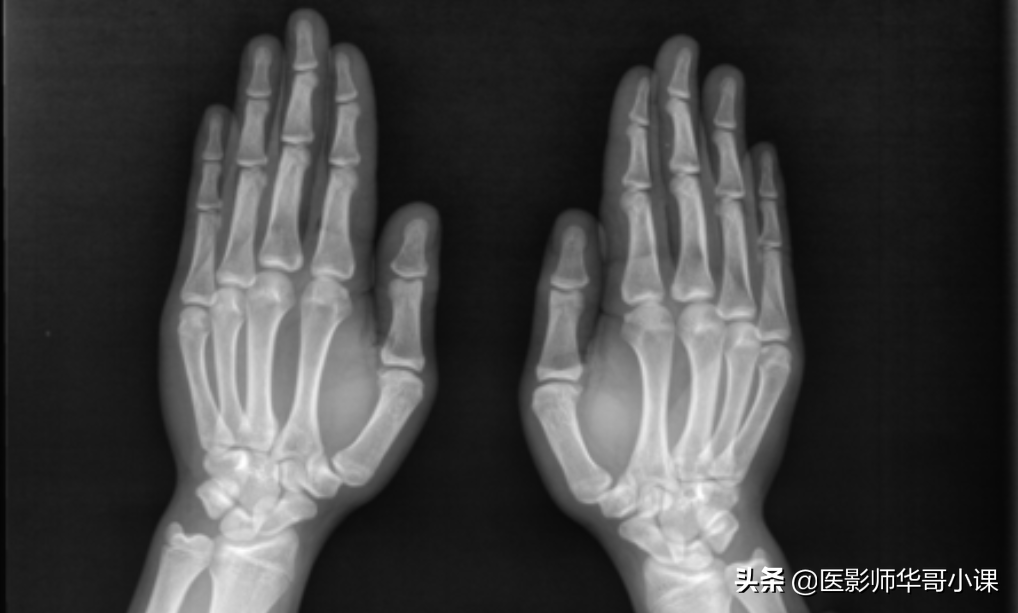

第一节 手和腕

1末节指骨的远端稍肥大,边缘不整齐是正常现象,第五指末节和中节指骨可能稍小。

2.中节指骨的掌面在指肌附着处粗糙不平,不可误认为骨质破坏。

3.拇指的基底节和其它手指的中节指骨可见到小的边缘锐利的卵圆形缺损,此为骨干的滋养孔,腕部诸骨由于滋养孔类似透亮缺损影,勿误为骨囊肿或破坏性病灶。

4.在一些正常儿童中,指骨骨骺中心的密度深浅不一,有的呈骨硬化密度,有的则很浅淡。这属正常现象,儿童第二至第五指指骨干骺端先期钙化带硬化或干骺端凹陷并硬化为正常变异所致。

5.第一掌骨和大多角骨之间的关节腔较宽,不可认为半脱臼。

6. 在很多正常儿童的第二掌骨近端骺软骨中可有副骨化中心,有时在所有掌骨近端亦皆有此种情况,即副骨化中心,可与骨干持续分离数年之久,最后在互相融合,亦有终生分离而成为一个独立的小骨者。

7.腕和掌部可有各种各样的副骨和籽骨,我国人只在第一掌骨远端可见有籽骨,其它部分副骨为籽骨及为少见。

8.钩骨的钩部在儿童期常见不到,但在青春期前都可显示出来,切勿把它当作分离的小骨折碎片,钩骨的钩部与体部在正位片上互相重叠,表现为局部密度增密度增高。

9.月骨早期可有两个骨化中心,以后可互相融合,或作为分离的小骨而存在,即月骨上小骨。有时月骨与三角骨互相融合,并在其融合部位形成一条假性骨折线。

10.双舟骨及三舟骨,手舟骨可由两点或三点化骨而形成双舟骨及三舟骨。双手舟骨的两半分界线在舟骨腰部,切误为骨折。(必要时可加照对侧)

11.腕豆骨是最小的腕骨,出现最迟,常由几个小骨灶骨化而成,可保持其颗粒状形态达数年之久。因此,在诊断幼年腕豆骨骨软骨炎时须谨慎,多角骨在发生的最早期可呈为粗糙而不规则的状态。

12.尺骨远端和腕骨间有三角软骨,因此,在正位片上尺骨远端距离腕骨较远,尤其在偏向桡侧的掌正位片上,尺骨远端和腕骨分离更远,容易被误认为半脱臼。

13. 婴儿出生后几个月内,大部分尺骨远端及少数桡骨骨端可见到一种杯状的横面,代替了常见的平直横面。这些生理性的杯状阴影,不要误认为佝偻病性的杯状阴影,在正常儿童期的后阶段,尺桡骨末端可呈波浪形的不规则表面,而其它骨的末端表面则仍显示光滑。尺桡骨茎突分离的骨化中心也很常见,不要误认为骨折碎片。